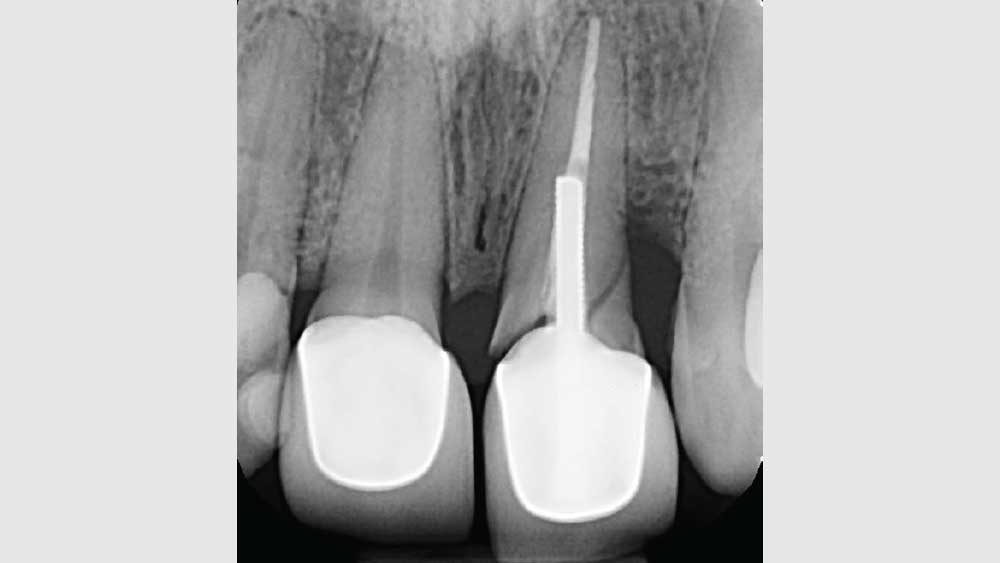

BRIDGING THE GAP WITH BRUXZIR® ESTHETIC

After conducting a thorough diagnostic examination, a vertical root fracture was noted, leaving the #9 central incisor malaligned and unstable. Due to the presence of significant vertical bone loss, extensive treatment for guided bone regeneration and a connective tissue graft would have been required prior to implant placement. After the patient was consulted on these factors, she opted against implant treatment. Once we discussed the remaining options, she decided on a bridge from #8–11 and a veneer on #7. Because she was congenitally missing tooth #10, placing a bridge to restore the edentulous area required preparing the adjacent canine and reshaping it to look like the missing lateral. I selected BruxZir® Esthetic Solid Zirconia as the best material to restore her beautiful smile. Not only does BruxZir Esthetic have superior strength compared to similar all-ceramic materials such as IPS e.max®, but it also has a translucent, natural-looking appearance. Sometimes clinicians think it is risky to do an all-ceramic bridge, but with a strong material like BruxZir Esthetic that has an average flexural strength of 870 MPa, doctors can confidently seat an anterior bridge that will produce long-lasting results. BruxZir has become such a popular material for dentists that it has been utilized to successfully fabricate more than 1.2 million bridges.